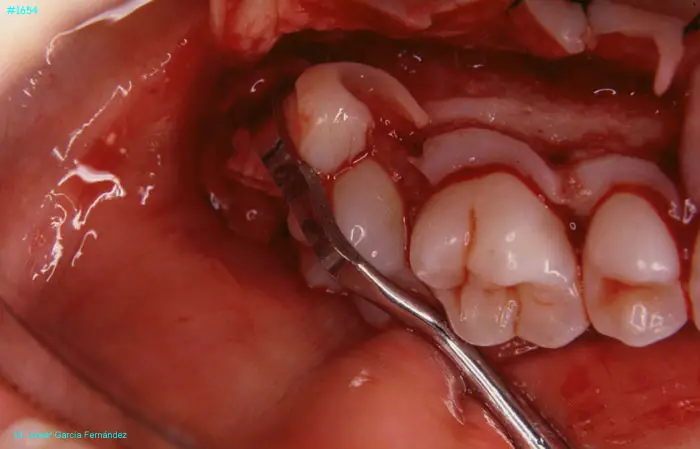

Atlas of Surgical Techniques in Periodontics. Chapter IV. Atlas de Técnicas Quirúrgica en Periodoncia

image 167